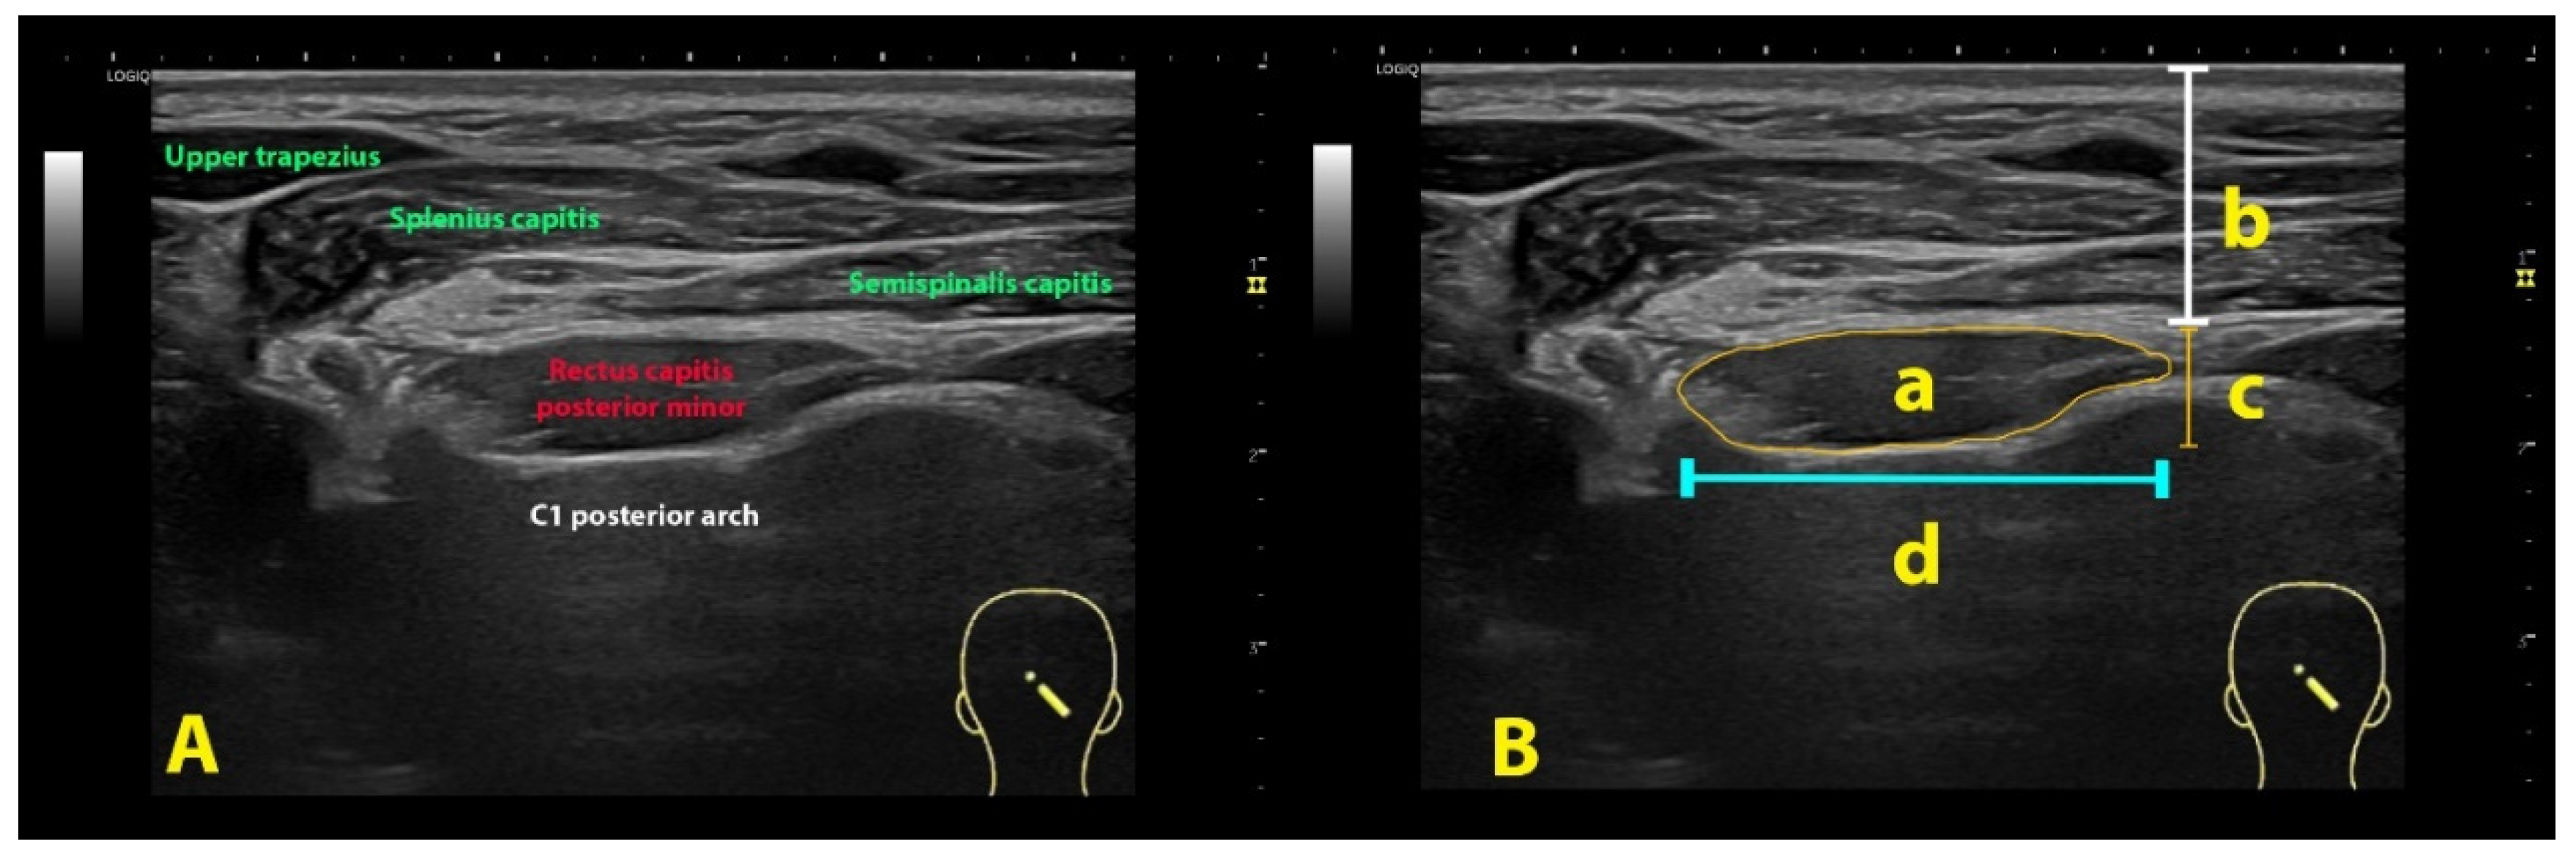

2.3. Ultrasound Assessment

2.4. Imaging Management